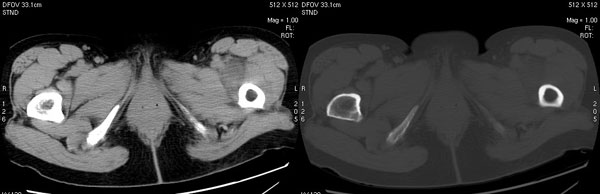

以下是引用jiajie在2006-7-14 17:19:00的发言:[br]ct所见:双侧髋关节不对称,左侧关节间隙变窄,关节面毛糙。左侧股骨头变形、无明显变小,前上缘与髋臼融合,融合处骨质明显增生硬化,并见数个小囊变影。股骨头下端与股骨颈交界部见囊样变,邻近肌肉内见囊样密度减低区,ct值24hu。右侧髋关节形态未见异常。[br][br]ct诊断:左侧髋关节结核可能,请结合临床资料进一步分析。

以下是引用lihuuuu在2006-12-5 10:14:00的发言:[br]定位像示:左侧髋臼变浅,倾斜度加大,髋臼外上缘呈波浪状不规则,骨质增生硬化,髋关节上缘间隙明显变窄,股骨头向外上轻度移位。轴位像示:左侧股骨头变形,前上缘与髋臼融合,融合处骨质明显增生硬化,并见数个小囊变影。股骨头下端与股骨颈交界部见囊样变,邻近肌肉内见密度减低区,ct值24hu,内缘见弧形高密度钙化影。右侧髋关节形态未见异常。[br]ct诊断:左侧髋臼发育不良[br] 左侧股骨头缺血性坏死[br] 左侧肌肉内低密度影伴有高密度钙化-考虑早期骨化性肌炎[br] [br]“我认为在描述上已经写了肌肉部分,印象诊断里应该写主见”[br]